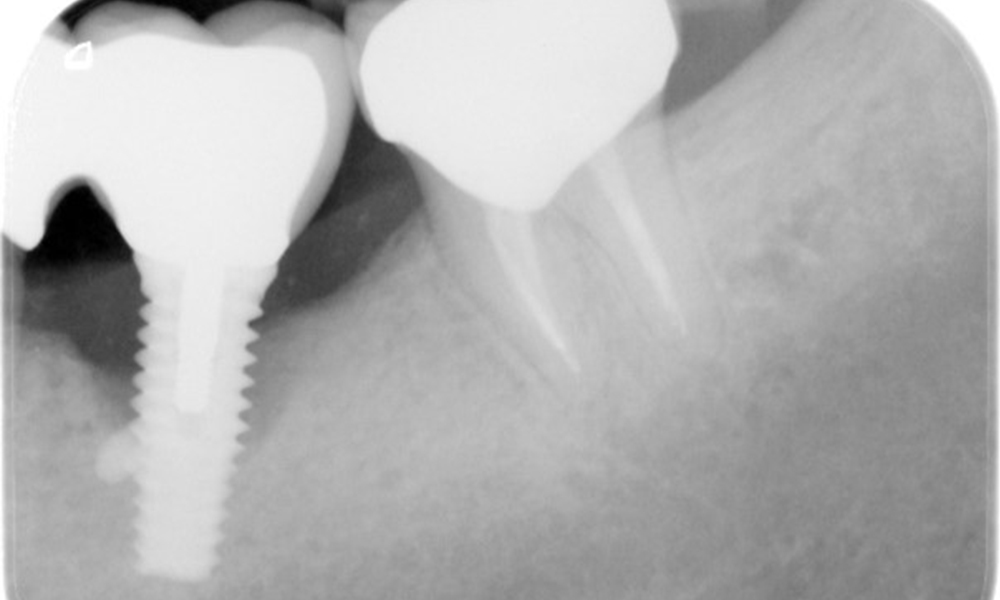

A 52-year-old patient presents at a preventive care session. The patient has no systemic disease and is not taking any medication. He has had various dental treatments and also has two active carious lesions. In addition, the patient has four implants (2nd, 3rd and 4th quadrants). He is revealed to have early periodontal disease (stage IV, grade B). His periodontal condition is stable; a probing depth of Probing depths (ST) of 5 mm is only evident at the implant in region 36. Gingivitis is also identified.

The patient has no particular risk factors with specific dental implications in his medical history. The key factor, therefore, is the requirement in terms of oral health. In this respect, there is evidence of a probing depth of 5 mm at the implant in the 3rd quadrant and, on the X-ray image, increased bone loss. The patient also has currently stable early periodontal disease and two active initial carious lesions.

In terms of instruments, specific procedures are required for use with implants. In order to preserve the surface of the implant while cleaning it effectively, it is essential to choose suitable powders and instruments, such as the targeted use of air polishing devices with special periodontal tips. Which powder is most suitable can be determined according to the needs and risk. For example, in addition to the appropriate degree of abrasion, dietary requirements (including sugar-free, low-salt) may also be taken into account.